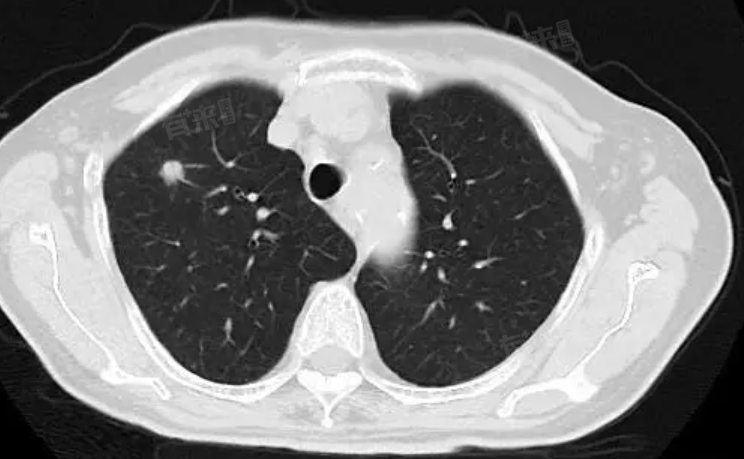

右肺斜裂小结节的严重性取决于结节的性质、患者症状与体征以及随访观察的结果,对于无症状、结节较小且良性可能性大的患者来说,一般不严重,不必过于担心,但需要定期复查以监测结节的变化情况。而对于有症状、结节较大或怀疑恶性病变的患者来说,可能比较严重,需要及时就医进行进一步检查和治疗。

- 性质:右肺斜裂小结节可能是良性的,如由肺部感染、肺结核等疾病遗留的病灶,也可能是恶性的,如肺癌或肺内转移癌。结节的性质是决定其严重性的关键因素。

- 大小:一般来说,结节越小,良性的可能性越大。对于0.4cm或更小的结节,如果没有其他症状或恶性征象,通常被认为是良性的,且不严重。

- 无症状者:如果患者没有胸痛、咳嗽、呼吸困难等症状,且结节在影像学上表现为边缘光滑、密度均匀,那么一般不必过于担心,但需要定期复查以监测结节的变化。